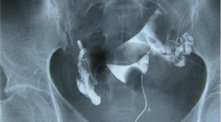

(一)查输卵管 输卵管通畅性的检查选择项目

怎么查:用导管注入造影剂

查多久:30-60分钟

必要性:输卵管堵塞占不孕70%,必查项。 咨询专家 -